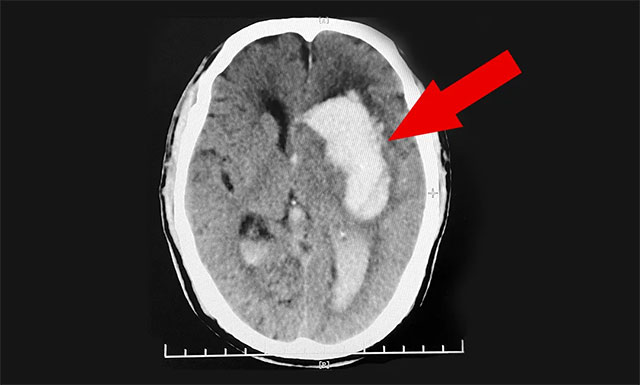

送到医院后,紧急行头部CT检查,根据影像提示及其他相关检查,患者程先生左侧基底节区脑出血,并破入脑室,且出血量很大,临近功能区;伴左侧高颅压,其双侧大脑半球深部多发腔梗,情况非常危急。医生把情况告知郭女士,若手术治疗风险很大,即使保住了生命,也很可能长期偏瘫在床,让她及家属做好心理准备。郭女士听后感到“天塌了一般”,简直无法接受。

▲ 患者突发脑出血昏迷不醒,病情危急需及时手术